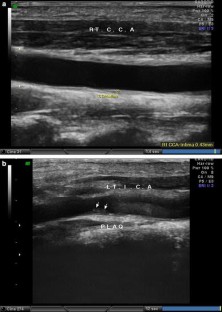

Fig. 1

Fig. 2